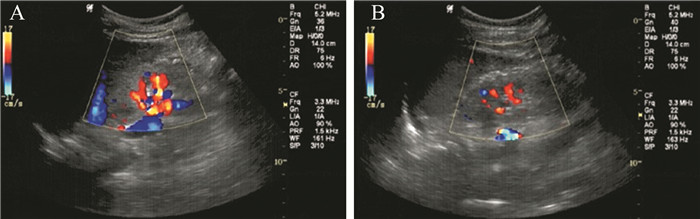

二、实验室及辅助检查血常规:血红蛋白91 g/L,红细胞3.2×1012/L,白细胞6.6×109/L,血小板148×109/L,血细胞比容0.279。血清白蛋白12.4 g/L。血尿素氮24.0 mmol/L,血清肌酐892.4 μmol/L,血钙1.81 mmol/L,血磷2.31 mmol/L。血清总胆固醇8.44 mmol/L,甘油三酯2.0 mmol/L。生长激素0.72 μg/L(参考正常值范围1.3~17.0 μg/L),甲状旁腺激素30.9 pmol/L。尿常规:尿蛋白(+++),潜血(+)。尿蛋白/尿肌酐比值22 746 mg/g。肾脏彩色多普勒超声(彩超):右肾大小82 mm×34 mm,皮质厚度9 mm,左肾大小85 mm×34 mm,皮质厚度9 mm;双肾轮廓尚清晰,体积偏小,形态正常,包膜光滑,皮髓质分界欠清晰,皮质回声增高,欠均匀;双肾集合管系统未见明显分离,其内无明确光团(图 1)。考虑双肾弥漫性改变。

图 1 该例肾病综合征患儿的双肾彩超图像 |